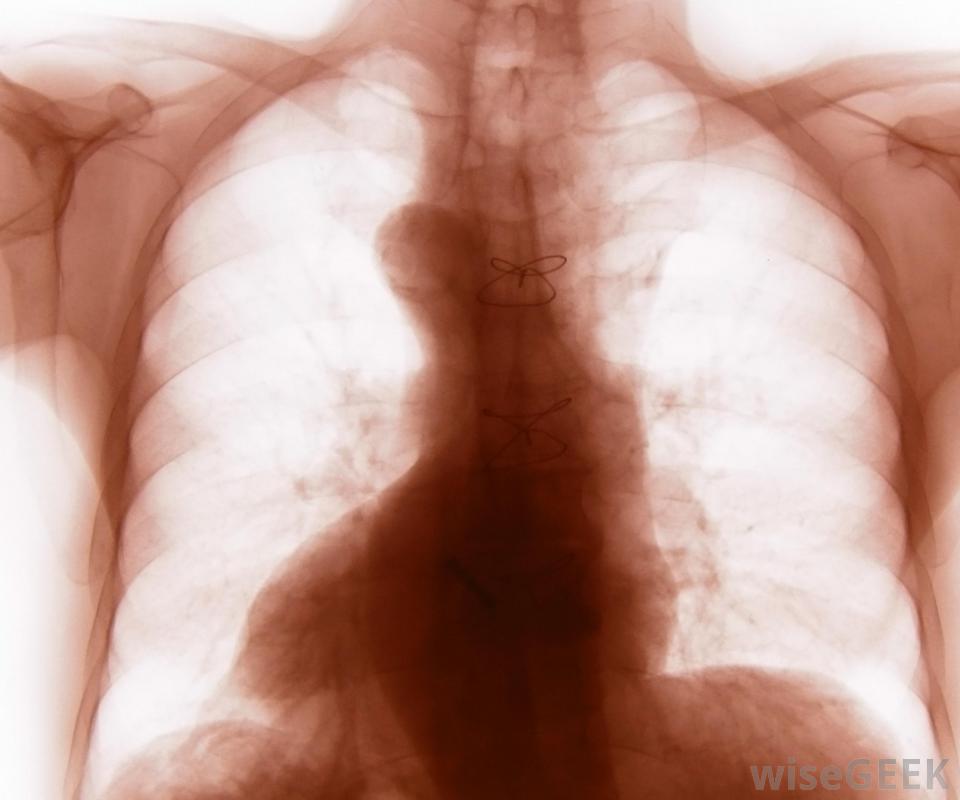

胸腔包括12对肋骨,胸骨和12个椎骨。第八、第九和第十对也环绕在身体前部,但是连接到胸骨的软骨是共享的,而不是单独的一块,第11对和第12对肋骨没有前部附着物,这就是它们通常被称为"浮动"肋骨的原因胸前胸腔的插图和X光片可能只显示第11对肋骨的一部分,而第12对肋骨往往很短,除了从身体的侧面或背面看,它根本看不出来。

第12对肋骨可能在X光片上看不到外行人士不应期望能够触碰到漂浮的肋骨对或构成胸腔一部分的肋软骨。肋骨任何部分的骨折都可能导致极度不适和胸腔器官损伤例如,汽车事故可能会导致一个人的胸部突然受到方向盘的强力挤压,导致一根或多根肋骨骨折,可能刺伤心脏、肺、肝脏或胃,导致内出血可能进行胸部影像学检查以诊断胸部损伤,除了休息、冰和非甾体抗炎药之外,很少有治疗方法可用。